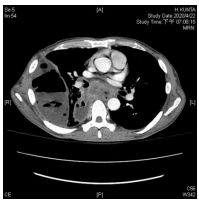

13. 47 y/o male; CC: intermittent fever for 2 weeks